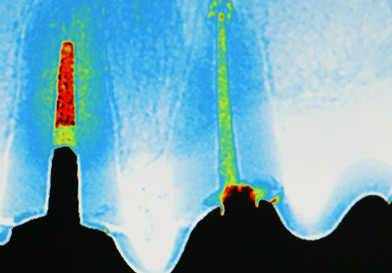

Unsere Praxis ist mit digitalen CCD Röntgensensoren der neuesten Generation ausgestattet. Diese ermöglichen gegenüber der konventionellen zahnärztlichen Röntgentechnik eine Reduktion der Strahlendosis um bis zu 90%. Darüber hinaus sind Auflösung und Kontrastverhalten der Bilder konkurrenzlos. Dies ermöglicht eine extrem schonende und exakte Diagnostik.